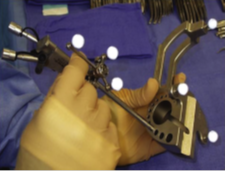

1) MARCO ESTEREOTAXIA: Marcación estereotáctica para lesiones profundas , craneotomias guiada por estereotaxia y/o asistidas por Neuronavegación. (Incluirá el equipo)